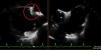

In the procedure, the middle portion of the interatrial septum was punctured (Figure 3) and PMV was performed first by the usual technique with a Mullins sheath and a Brockenbrough needle and inflation of a 26 mm Inoue balloon (Figures 4 and 5), with a good result (absence of transmitral gradient, 2.1 cm2 mitral area and no increase in the degree of valvular regurgitation). Percutaneous LAA closure was then performed. Keeping the guidewire in the same transseptal puncture, a pigtail catheter was introduced into the LAA to allow selective injections into this structure (Figure 6). A 30 mm Amplatzer Cardiac Plug (ACP) (St. Jude Medical), specific for percutaneous LAA closure, was inserted via the ACP release sheath and implanted in the left appendage. It was released successfully and without complications (Figures 7 and 8).

The patient was discharged on indefinite treatment with acenocoumarol, associated with aspirin (100 mg/d) for three months. After one year follow-up there have been no further embolic episodes or other complications (Figure 9).